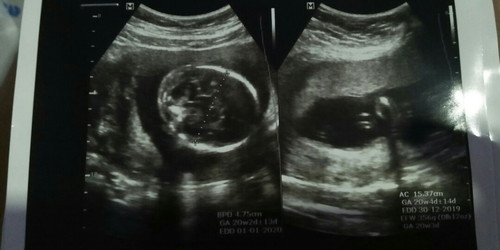

halo bun.. .mau sharing dong td pagi saya abis usg bulan ke 5 kehamilan,tp hasilnya lebih jls usg yg bulan ke 4 si. .kta dokter air ketubannya byk,tp debaynya sehat puji Tuhan. Disini ad yg bsa baca hasil usg ga ya? .minta bantuannya dong,biar lbh tenang. msi penasaran soalnya ga bsa tnya lama" td wktu kontrol?

air ketuban banyak,baik/tidak?